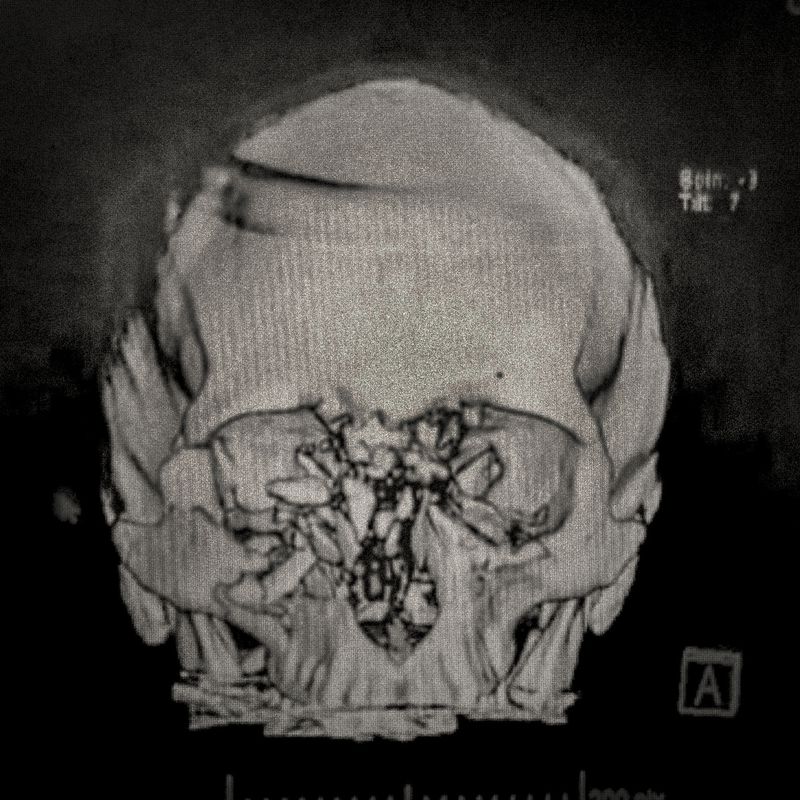

X-ray showing the pellet embedded in the skull of Ybar Soto (29) Ybar was hit by a pellet that lodged in his right eye on October 24, 2019 in Plaza Italia. Santiago. His diagnosis was ocular burst. Santiago, Chile. December 28, 2019